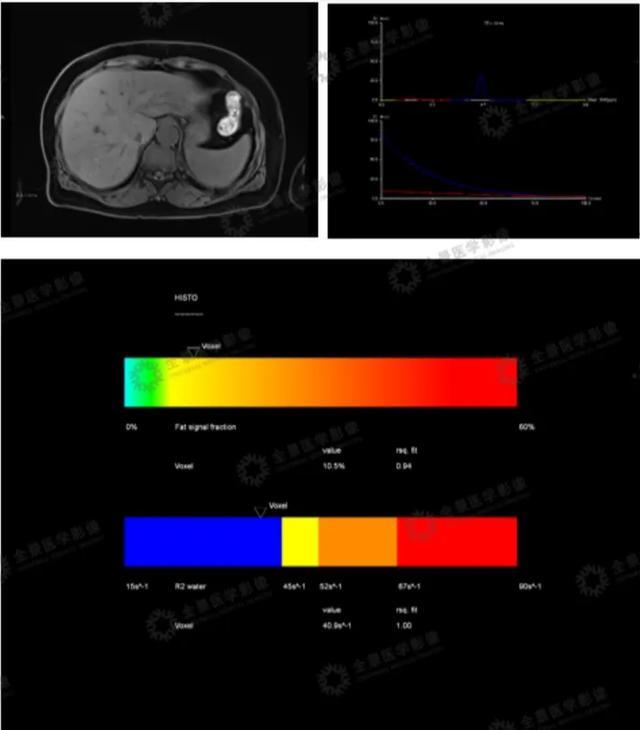

上腹部磁共振能对肝脏内脂肪程度进行定量分析,精准量化,客观认识自身健康,提高健康意识,还能根据脂肪肝分级标准:轻(5%-10%)中(10%-25%)重(>25%)度脂肪肝作为脂肪肝含量参考,结合临床症状及实验室检查,确定治疗方案,适用于消化内科、内分泌科、中医科等,与脂肪肝发病率高的相关科室。